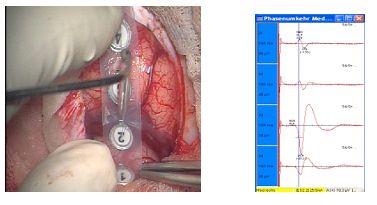

Eine exakt lokal funktionelle Darstellung motorisch relevanter Hirnareale lässt sich seit einigen Jahren  mit einer weiterentwickelten Technik der MEP, der sogenannten Navigierten Transkraniellen Magnet Stimulation erreichen. Dabei kann in Vorbereitung einer Operation im Bereich der Zentralregion, die funktionelle Zuordnung bestimmter Muskeln in repräsentativen Hirngebieten aufgezeigt werden und die Lokalisation einer Raumforderung in Bezug gebracht werden. Zugangswege werden dadurch sicherer planbar. Die gewonnen Ergebnisse lassen sich durch Einspielung der Daten auf das Navigationsgerät auch intraoperativ nutzen.

NTMS- Navigierte Transkranielle Magnetstimulation